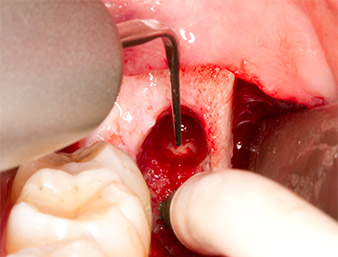

A continuación, se utilizó un inserto para la retirada de los sedimentos periodontales (Piezomed P1) y se amplió mínimamente el surco periodontal del resto radicular (figura 8).

El mismo inserto activado se introdujo en el canal radicular y aflojó el fragmento gracias a sus vibraciones microoscilantes (figuras 9 y 10).